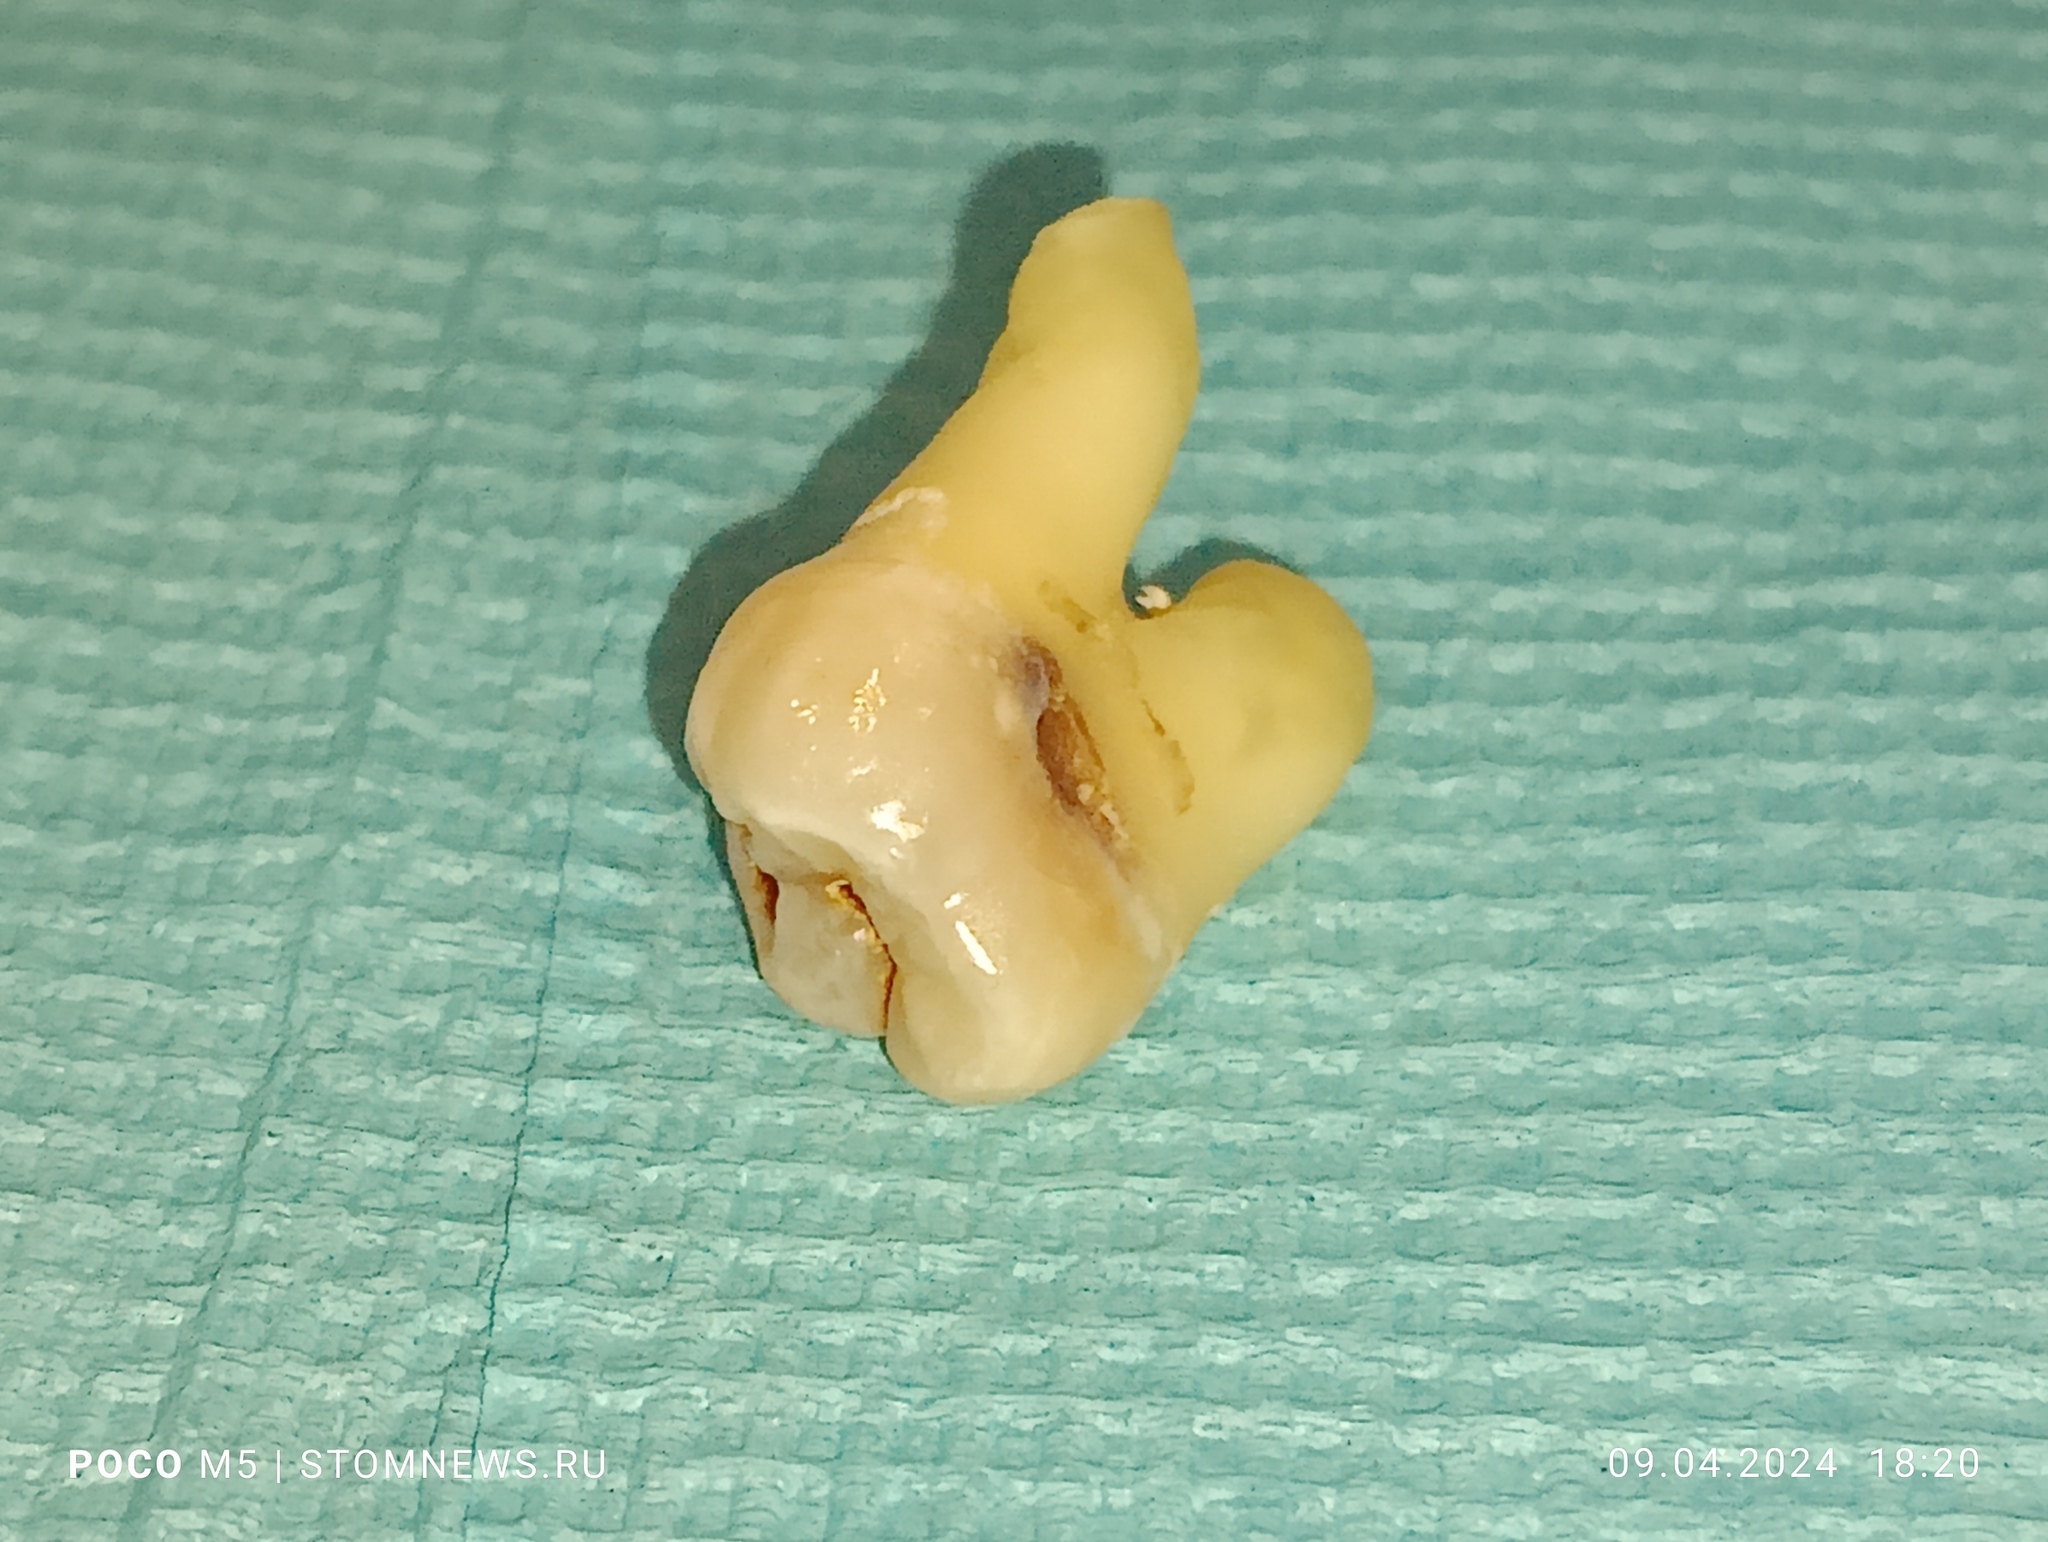

Удаленный 28 зуб мудрости с корнями по типу «оленьи рога»

💥Вот такой клинический случай произошел у меня на приеме сегодня: 09.04.20024 💥

😬Как оказалось, у пациента слева вверху запряталась восьмерка, которая только не давно прорезалась. При пальпации слизистой в области 28 зуба пациент резко дёргался 😱😱😱

☄️Было принято решение об удалении, так как спасти его не представлялось возможным👊

✌️Я решил сделать серию фотографий и выложил их на свой собственный сайт в виде галереи. Если вам интересно посмотреть поближе на этого монстра, то переходите по ссылке ниже👇👇👇